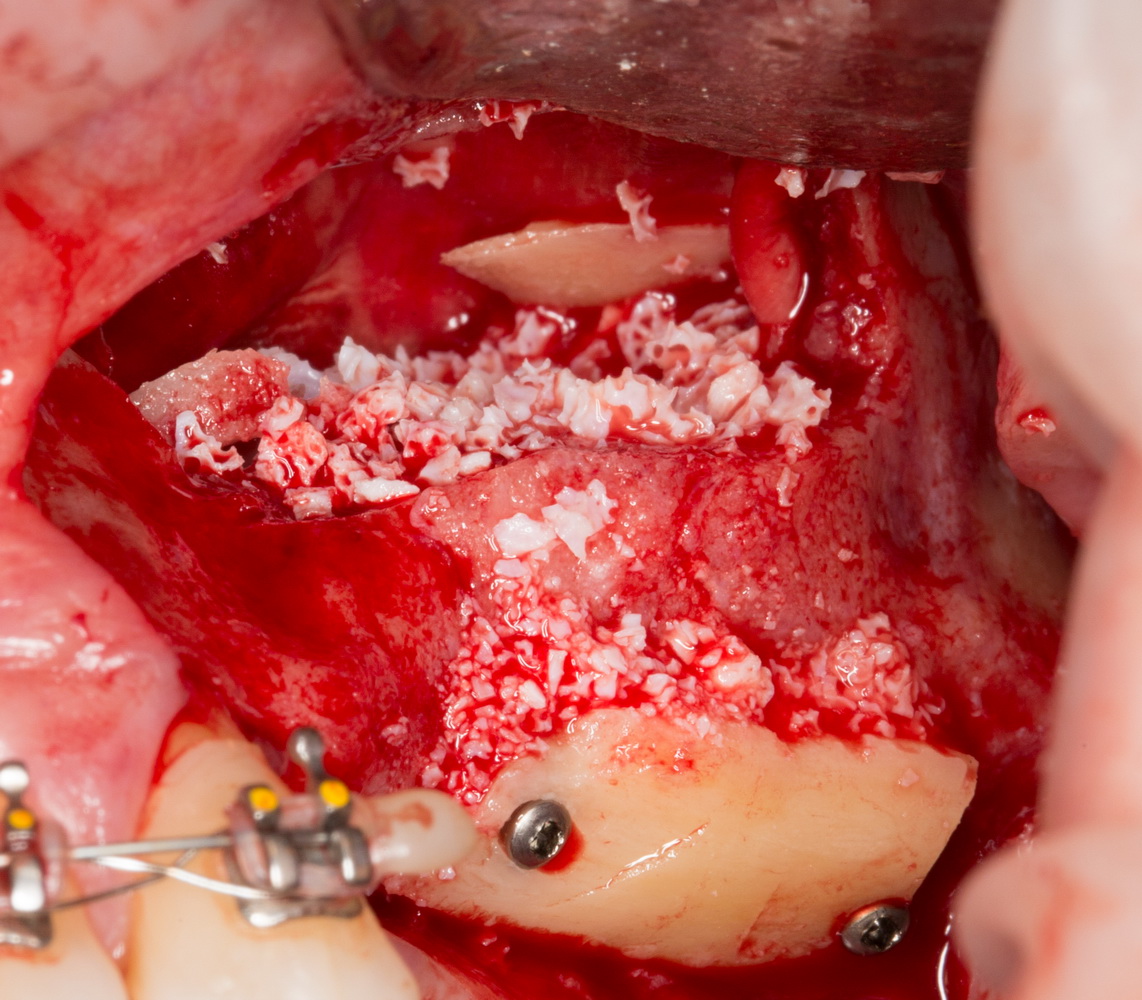

Другой метод остеопластики называется «направленной тканевой (или костной) регенерацией». Для успешной его реализации необходимы барьерные мембраны, нередко — дополнительные биоматериалы, пины и т. д., что существенно (иногда в два раза) повышает стоимость хирургического вмешательства. Но живые клетки — основа регенерации костной ткани, — в этом случае забираются в виде аутокостной стружки, а не блока, поэтому травматичность данного метода ниже, чем при аутотрансплантации. Результаты, предсказуемость, надежность — те же самые:

Еще существуют комбинированные методики остеопластики, но они применяются в ситуациях существенной утраты костной ткани, когда аутотрансплантация костных фрагментов или направленная тканевая регенерация не могут обеспечить достаточные объемы восстановления кости: